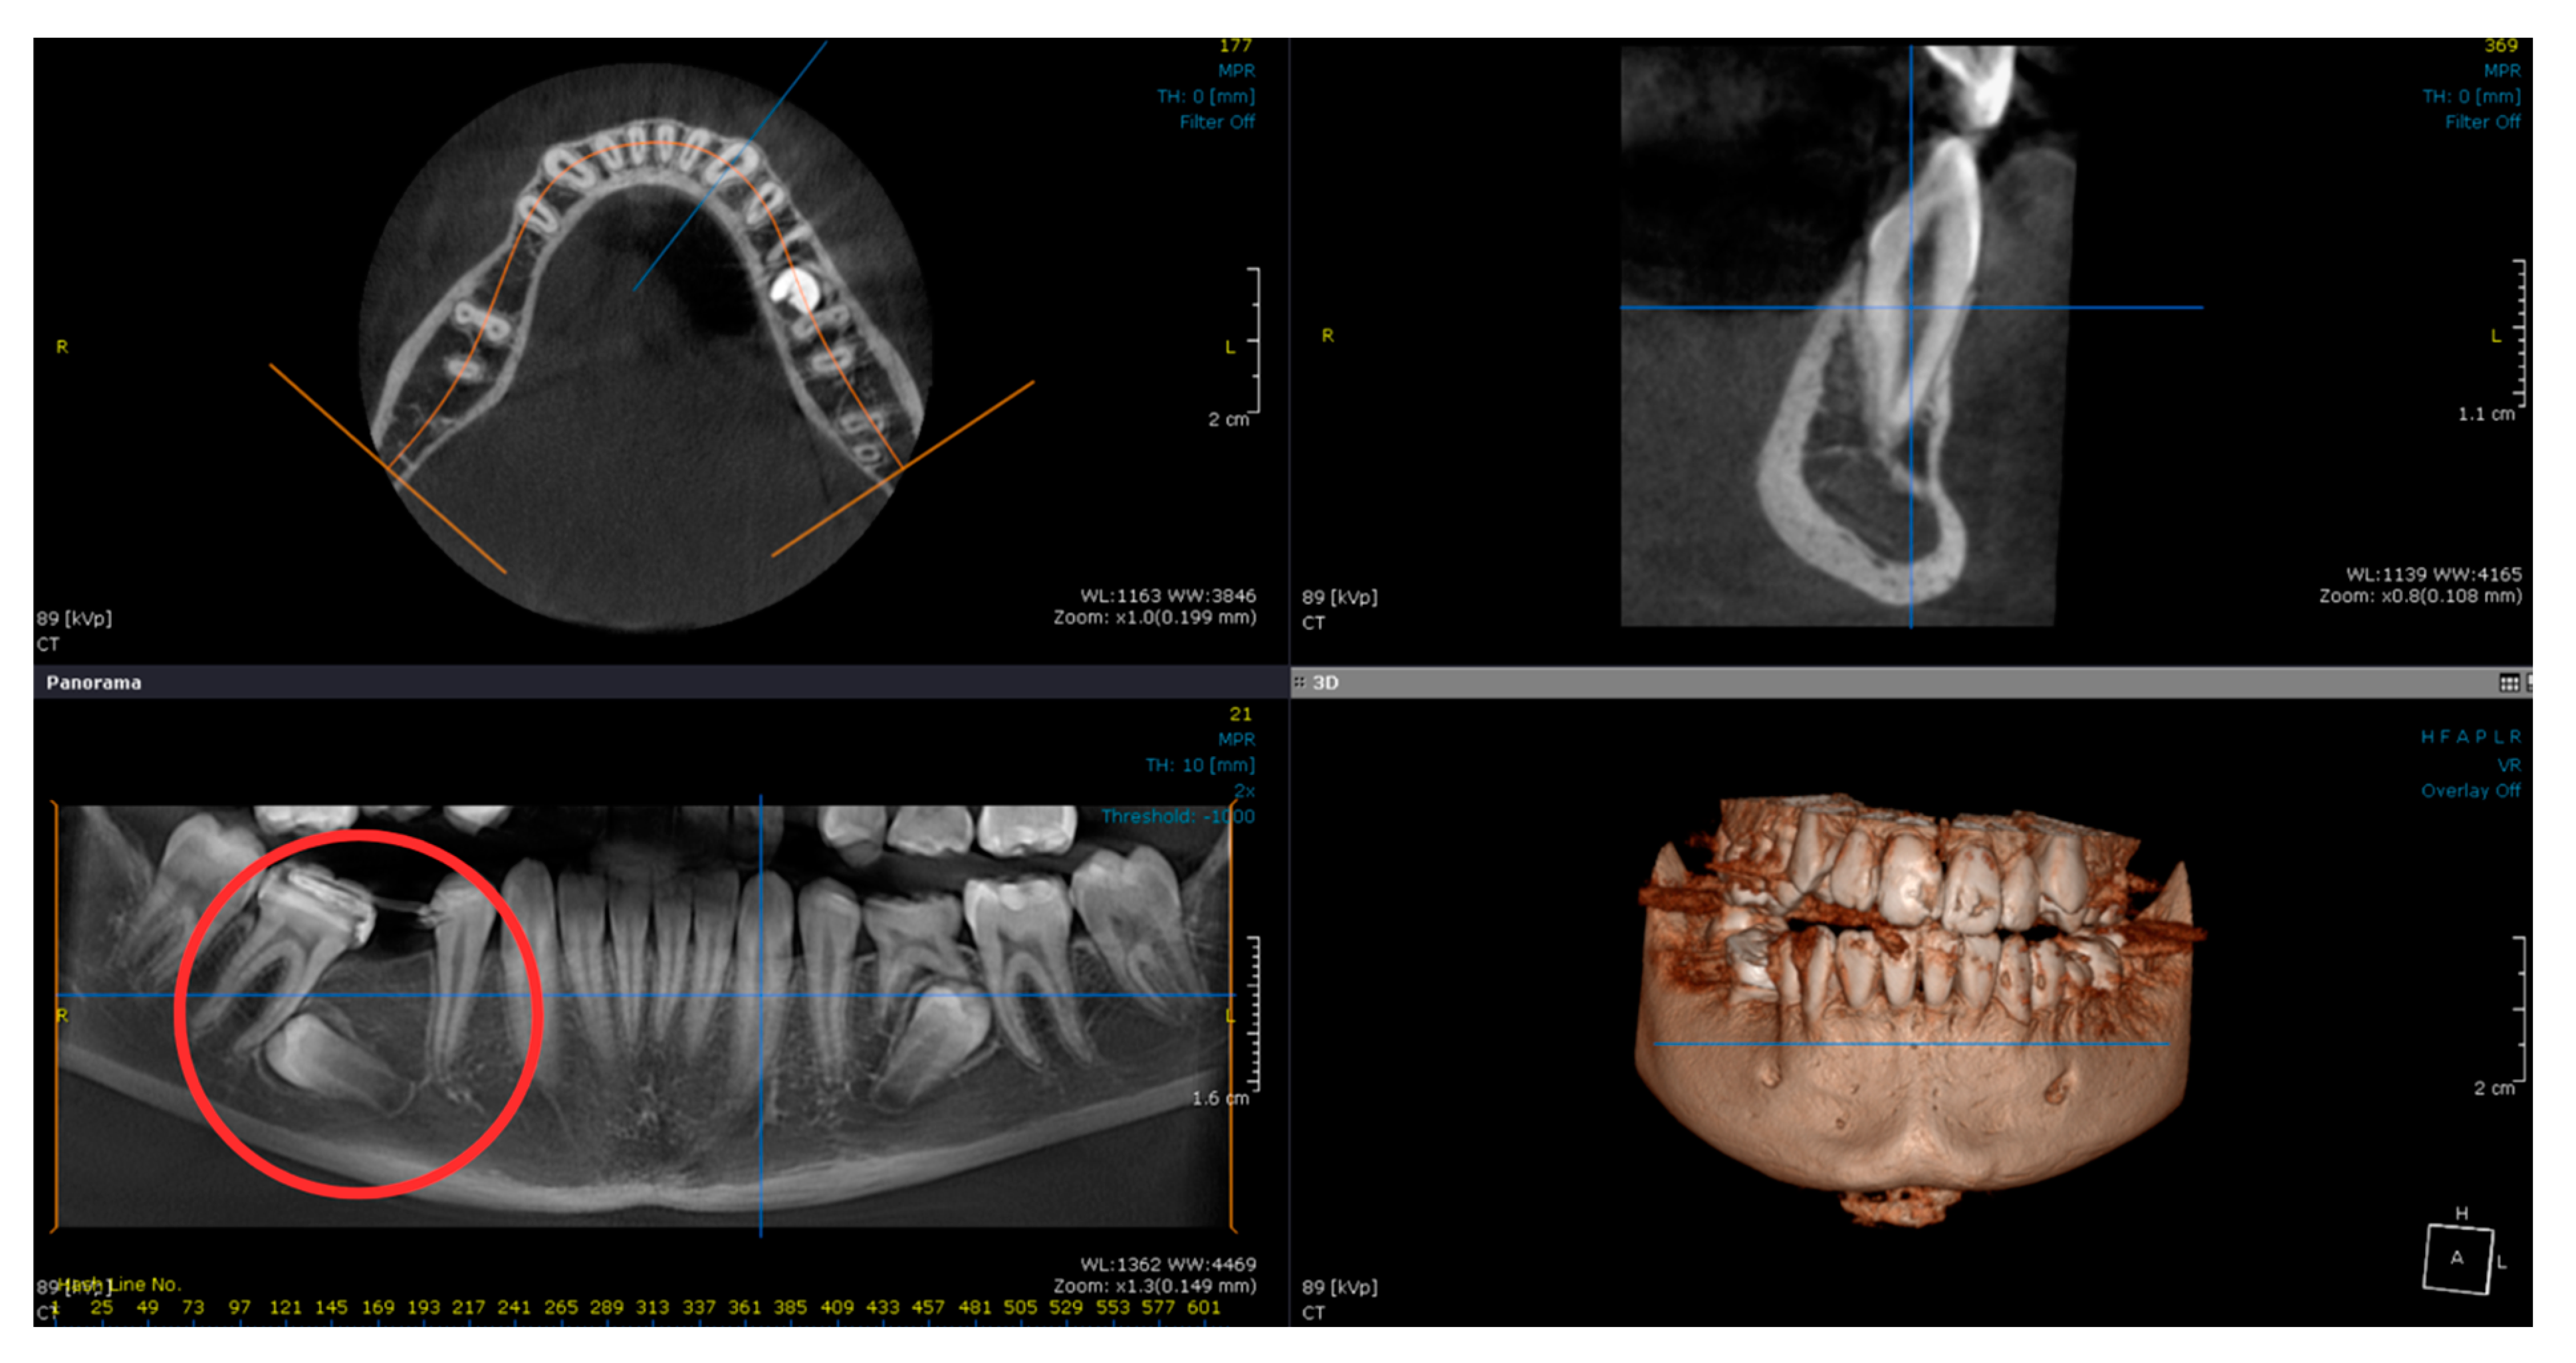

2.1. Examination, Diagnostics, and Initial Therapeutic Management